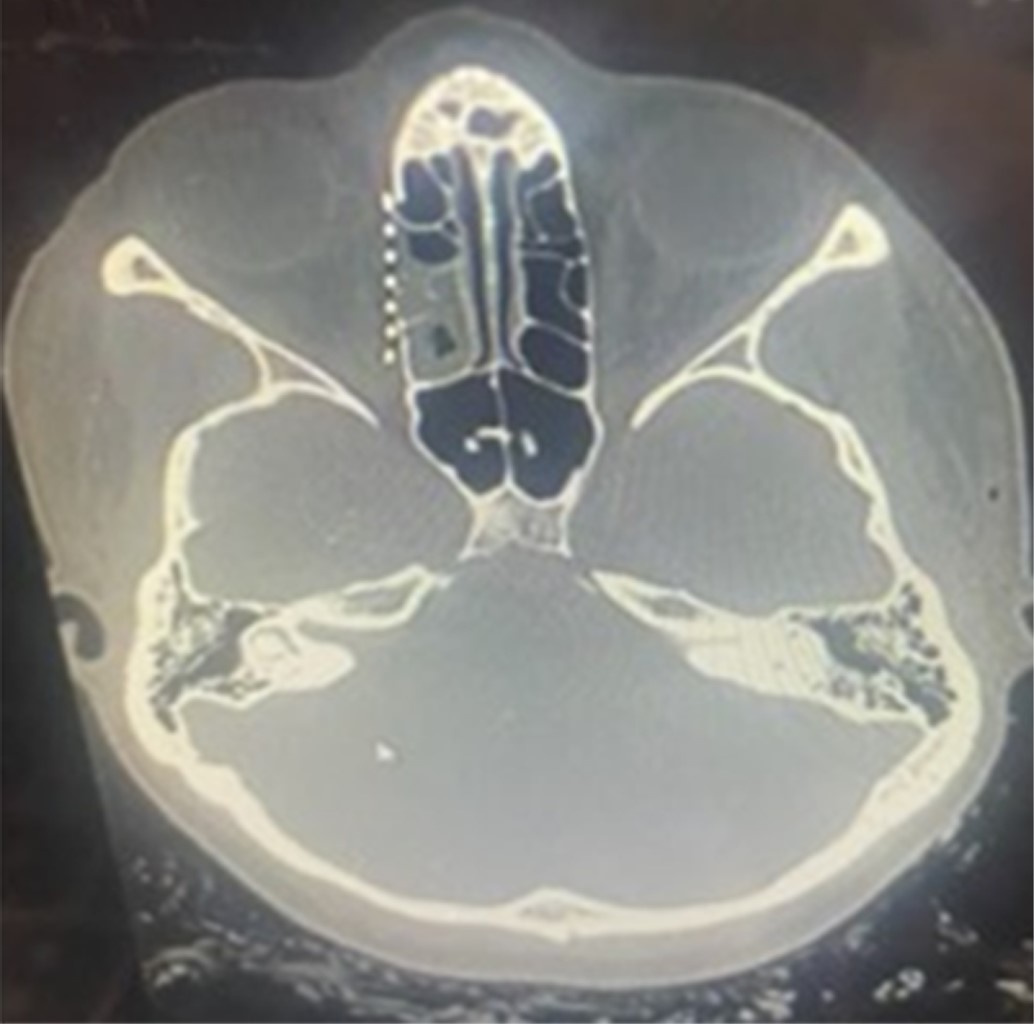

Una tomografía computarizada de la cara mostró una fractura de tipo Le Fort I del suelo, de la pared medial y del techo orbitario bilateral, fractura del cigomático derecho y de la pared anterior del hueso frontal.

Bajo anestesia general, el paciente fue intervenido cinco días después del traumatismo para la reducción y fijación de las fracturas realizando un acceso bicoronal (Figura 1), infraciliar bilateral, sutura frontozigomática del lado izquierdo y acceso intraoral de Caldwell-Luc en fondo del saco superior del lado derecho. Las fracturas orbitarias bilaterales se reconstruyeron con malla de titanio en el suelo, la pared medial y el techo orbitario; todas las fracturas se fijaron con placas y tornillos del sistema de 1.5 mm; se realizó una prueba de ducción forzada con pinzas Adson y la movilidad del globo terráqueo fue satisfactoria (Figura 2).

En la tomografía computarizada postoperatoria de la cara se puede observar la reconstrucción de las fracturas del seno frontal, del techo, de la pared medial y del suelo orbitario y sus respectivas fijaciones (Figuras 3 y 4).